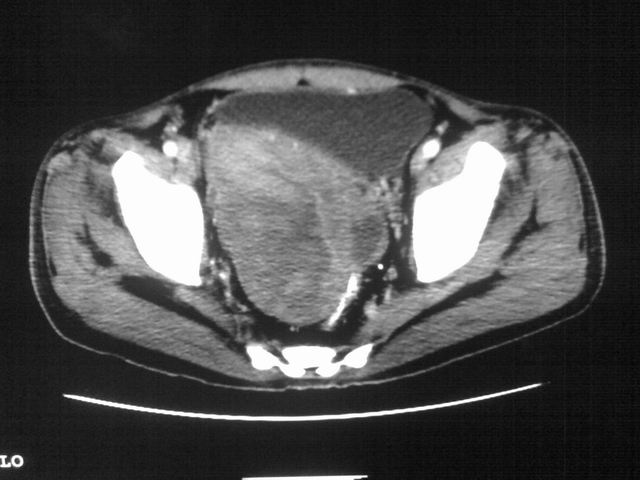

患者m 56岁,盆腔及下腹部胀痛半年,加重1月余,消瘦\中重度贫血.(附:平扫时直肠的高信号为,残留的钡剂).补一下病史:胃镜及纤维结肠镜均无明显异常.

首先是病灶的定位,平扫看很象肠管肿瘤但既然纤维结肠镜正常就可以除外结肠病变,增强成不均匀强化,位于右下腹部应该首先考虑回肠末段占位性病变,1淋巴瘤,2间质瘤,3腹膜后神经原肿瘤待除外,

首先是病灶的定位,平扫看很象肠管肿瘤但既然纤维结肠镜正常就可以除外结肠病变,增强成不均匀强化,位于右下腹部应该首先考虑回肠末段占位性病变,以间质瘤或淋巴瘤可能性大.,

膀胱及直肠间有不规侧的软组织密度影,内密度不均匀。其内有坏死囊变,前列腺及精囊腺,膀胱后壁受浸。结合病史考虑腹膜后肉瘤可能性大。